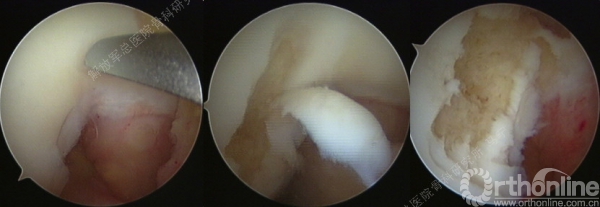

第一次手术-评估(关节镜评估及取种子细胞)。

缺损部位的标记:根据关节镜下的检查评估来确定损伤部位,范围,以决定二次手术的切口部位。

软骨组织的获取:关节镜下观察关节软骨的股骨髁间非负重区的穹窿部位或股骨滑车区边缘非负重部位,清理周围的滑膜组织,应用髓核钳或鹅眉凿获取患者关节软骨100-200mg。

术中所见和影像检查一致。

患者右膝疼痛6年,无绞锁,特别是蹲起困难,于2008年住我院,接受关节镜手术,发现股骨滑车局部软骨缺损。

患者,男,26岁,右膝关节间断性疼痛3年,关节屈曲经过40度时有弹响伴疼痛,发现股骨髁局部软骨缺损。损伤的软骨下骨可见明显水肿。

切开后可以看见很明显的软骨破坏。